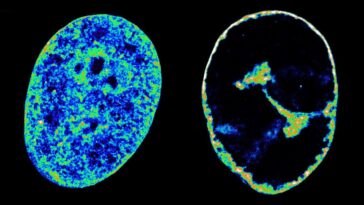

Comment les IRM peuvent détecter l'apparition de la maladie de Parkinson avant l'apparition des symptômes